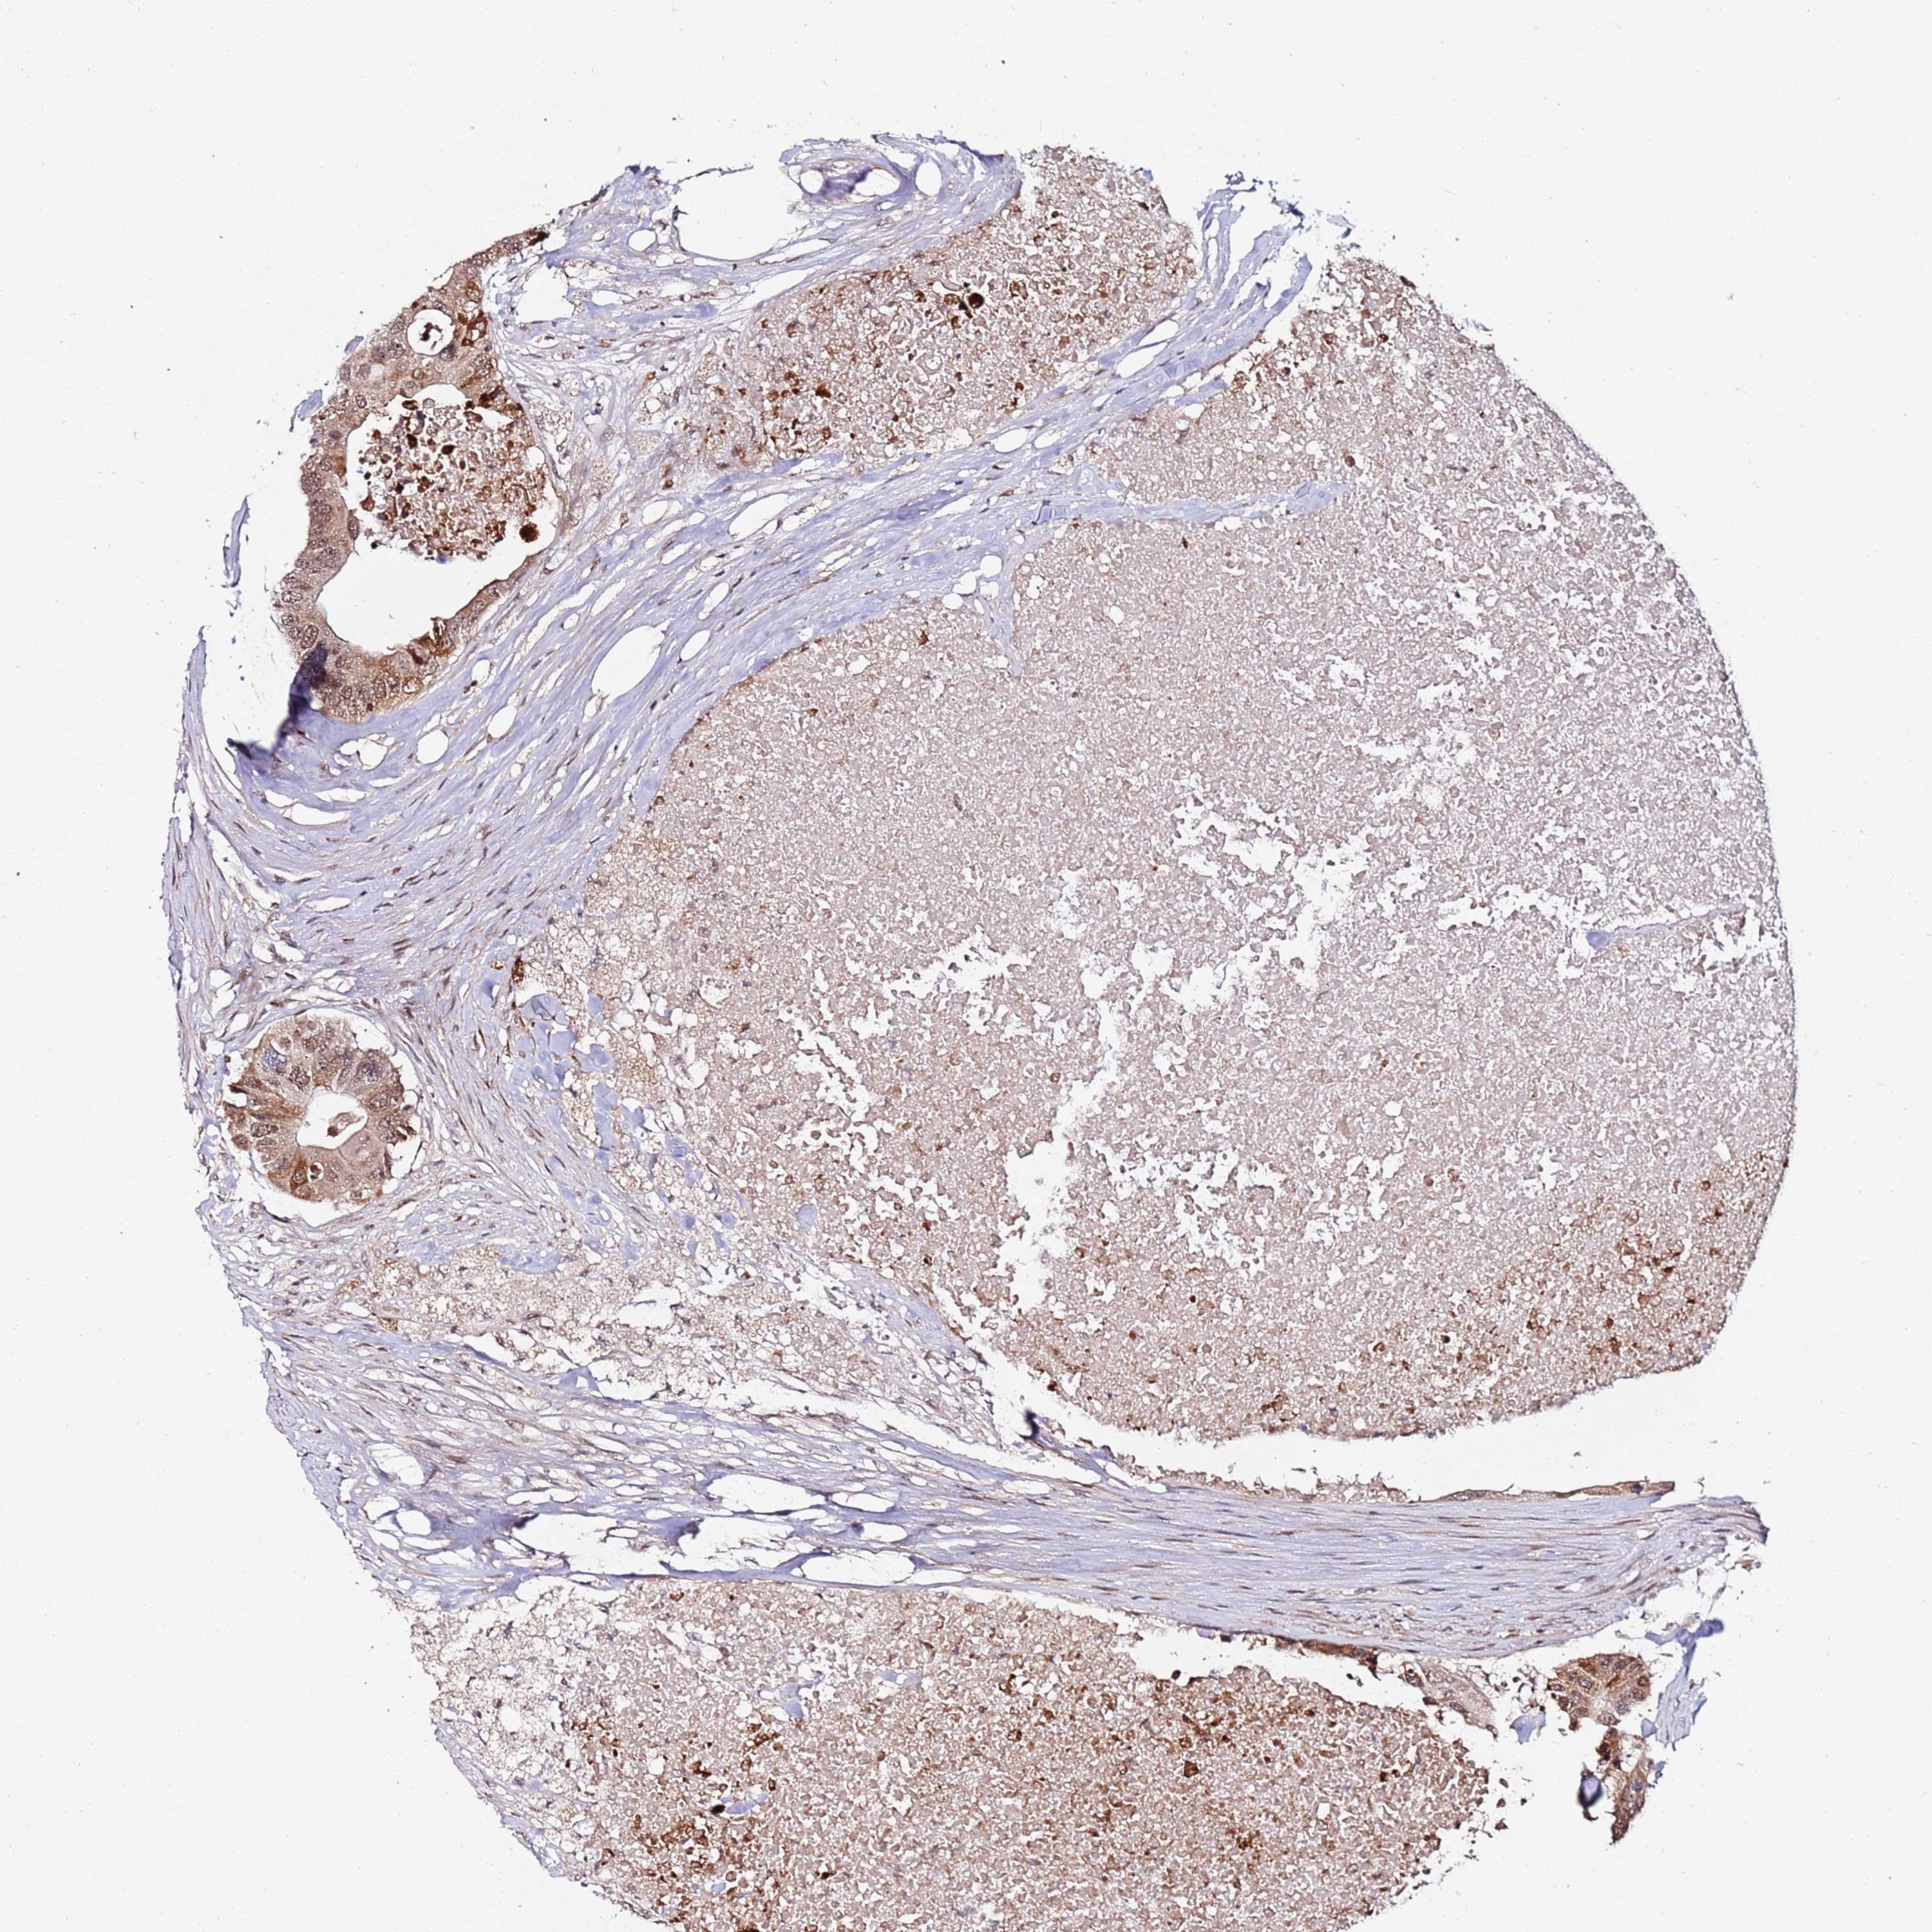

CANCER COLORECTAL CANCER Show tissue menu

Colorectal cancer

Human cancer